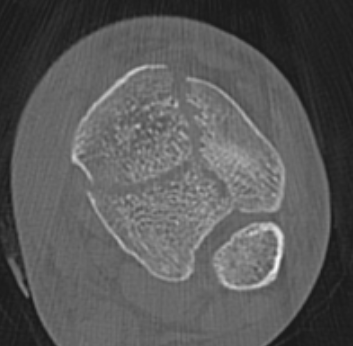

Commonly 3 fracture configurations

- medial malleolus

- posterolateral fragment / Volkmann

- anterolateral fragment / Chaput

Tibial plafond common fragmentsTibial plafond fragments